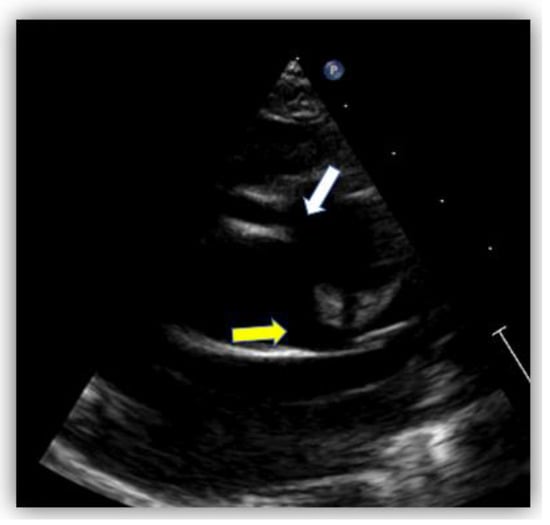

2. Case Report #1

| Echocardiography |